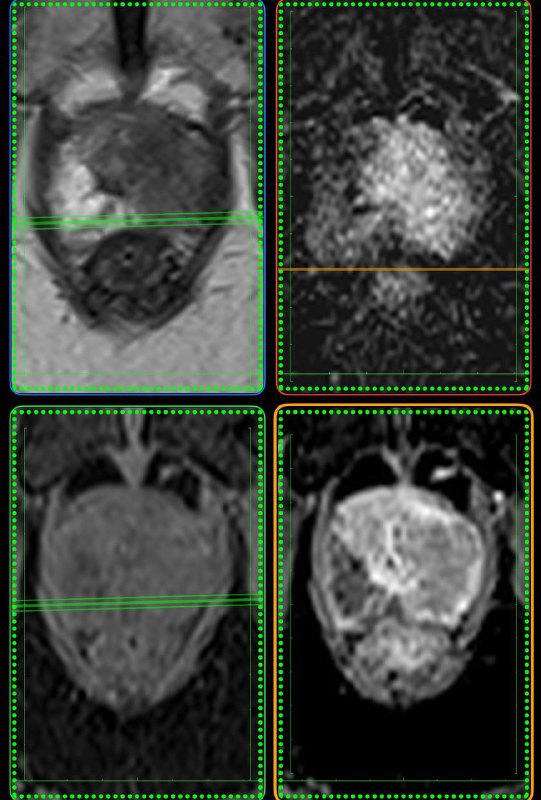

У пожилого мужчины после переохлаждения резко появилась задержка мочеиспускание, урологи утверждают, что у него – острый простатит. А на Магните – типичный рак, по крайней мере, PI-RADS 5.

Как считаете, может ли острый простатит выглядеть вот так? Асимметричный, с достаточно чётким контуром, да ещё и с быстрым накоплением контраста и быстрым же его вымыванием?

Что-то я сильно сомневаюсь, поделитесь опытом.

Когда рак простаты видно вот так, как здесь - исследование не вызывает отвращения, в отличие от случаев, когда приходится писать PIRADS-3..

Другое дело, что мы ж о пациентах заботимся, а не о себе, любимых, и каждый PIRADS-3 для пациента, все же, лучше, чем легко и непринуждённо обнаруживаемый, как в данном случае, PIRADS-5.

Пожелаем этому мужчине 75 лет успехов в лечении и минимума неприятных ощущений, которыми, неизбежно, такое лечение сопровождается.

Всем привет!

А вот для чего иногда нужен контраст на МРТ предстательной железы: по DWI, а она является основной последовательностью для оценки периферической зоны, типичные изменения ПИРАЦ-4 (наибольший размер - 12 мм), но вот на Т2 - жидкость, а не серость, и на постконтрастных накопления контраста нет вообще. Так что, это - абсцесс, а не рак.

Соблюдайте протокол и не будете разочарованы.